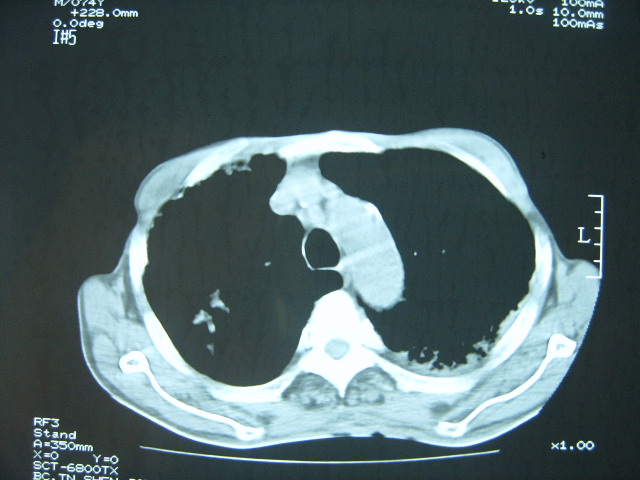

男74岁,咳嗽,寒战,低烧。有糖尿病史。

两肺结核,空洞形成,左下肺肺段隔离症待排

考虑:1、左下肺脓肿;

2、双肺结核。

考虑:糖尿病合并:1、左下肺炎继发肺脓肿;

考虑:1、左下肺脓肿;不排除霉菌感染

1、左下肺肺脓肿,合并霉菌球形成?.2、双肺陈旧性病灶.3、右上肺病灶警惕瘢痕癌,建议定期复查.

两肺结核,左下肺大片实变,内见空洞性病变,壁不规则,结合糖尿病史,考虑:结核性?霉菌性?建议结合实验室检查或治疗后复查。